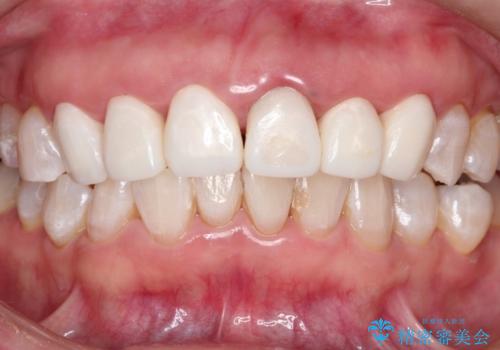

神経が死んで変色した歯 根管治療とオールセラミッククラウン